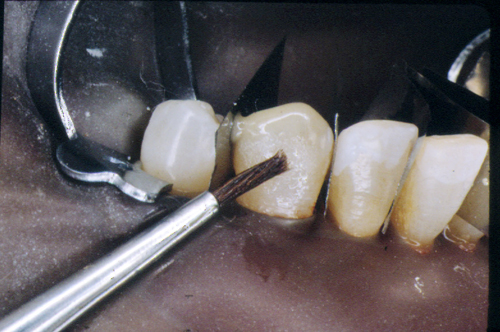

En ciertas áreas del saber humano, el lenguaje confuso o criptográfico Muchas son las técnicas elaboradas para lograr un desgaste selectivo, y numerosos autores han expuesto en su momento variadas formas de lograr una función oclusal fisiológica mediante el ajuste de la misma. Han pasado años desde entonces y, sin embargo, aún hoy, un altísimo porcentaje de profesionales “navega” por el mar de la confusión oclusal, dada la diversidad de conceptos y escuelas, sin lograr arribar a costa alguna donde poder anclar un conocimiento sólido sobre cómo tratar la oclusión Ya se esté realizando una simple obturación, endodoncia, incrustación, radectomía u ortodoncia, la lógica pocas veces, en la mayoría de los casos, vincula un tratamiento con otro, siendo el resultado final el mismo caos inicial; enmascarado por mucho tratamiento profesional. El ajuste oclusal es un medio inicial de proveer al sistema enfermo de: Dicha técnica, que puede ser terapéutica en sí misma; consta de dos etapas, a saber: 1) Ajuste Oclusal por Adición Mediante el estudio de la guía anterior, encargada de efectuar las Disclusiones durante las excursiones mandibulares, podremos observar si ésta es funcional o no. • Marcas de carácter continuo, si en ese recorrido se produce la Disclusión de los sectores posteriores y todo marcha correctamente. FIG 1-2 Si por el contrario observamos: • Marcas de carácter discontinuo, significa que dicha Disclusión se está efectuando por medio de una pieza dentaria posterior a la guía anterior. FIG 3-4-5 (FIGS. 3, 4 Y 5). En la figura 6 las flechas indican, en un caso clínico de análisis oclusal, la presencia de marcas discontinuas que indican Interferencias en Propulsiva. FIG 6-7 Y por último, si existieran: • Abrasiones de las áreas discluyentes en las áreas de diagnóstico de la guía anterior, deberemos aportar material a dicha zona para no permitir el choque lateral de las piezas posteriores (Ajuste Oclusal por Adición) En las imágenes 11 y 12 podemos observar la adición de composite en la punta de un canino derecho, previa la observación de la Faceta Parafuncional remarcada durante el análisis oclusal en el articulador. (FIGS. 8 A 12). 2) Ajuste oclusal por Sustracción o Desgaste Habiendo cumplido ya con la verificación de la funcionalidad de la Guía Anterior, comenzamos los desgastes en céntrica, a fin de lograr un único arco de cierre, guiado eficazmente por la Guía Anterior; es decir: la coincidencia entre Oclusión Habitual y Oclusión en Relación Céntrica. En este caso, intentar gastar dichos puntos, de ser posible sólo en las cúspides de corte o no fundamentales: • Crestas Triangulares Internas, Cúspides Vestíbulares Superiores • y un poco de las Crestas Triangulares Internas, Cúspides (FIGS. 13 A 16). Si la deflección es hacia el lado opuesto, se invierten los desgastes. En las migraciones hacia adelante, las únicas razones posibles están en los puntos estabilizadores (FIG. 17); es decir: -Vertientes Distales de los Rebordes Marginales, Triangulares (FIG 17) (FIG 18 A-B-C-D) Obsérvese cómo, en una boca prácticamente entera, comienzan a “desmoronarse” prismas adamantinos (FIG. 19), como consecuencia de un punto prematuro de contacto, ubicado en la posición de un estabilizador, que provoca la discrepancia horizontal postero-anterior causante de dicho efecto (FIG. 20). FIG 19-20 Dicho punto, será necesario ajustarlo antes de cualquier tratamiento en la zona ¿Cuáles serían las consecuencias si esos incisivos fueran implantados tal como es frecuente observar en múltiples congresos y cursos de implantología, donde el tema de la oclusión no es más que un cuadro polifacético y anecdótico? 14 15 16 17 Todo producto del adelantamiento mandibular Realizados ya los desgastes en céntrica, obteniendo de esta manera un único arco de cierre, es decir, oclusión en relación céntrica, debemos realizar el ajuste de las excéntricas, apoyando la acción de la guía anterior, para lo FIG 22 a. De un lado a otro de un mismo maxilar, la imagen es especular, o sea invertida. b. En hemimaxilares cruzados, la imagen es idéntica. Allí donde existan colisiones entre cúspides, se deberá crear un surco para que dicha cúspide antagonista migre a su través, tanto en el lado de no trabajo, como en el de trabajo y en el de propulsión. FIG 23 Es importante conservar esta parte del surco, ya que si no existieran, los contactos entre cúspides serían en superficie y no puntiformes (fig. 24). FIG 24 1. Obtener un único arco de cierre con coincidencia entre oclusión habitual y relación céntrica. 2. El cierre mandibular debe ser recibido sólo por la tabla premolar-molar. 3. Durante las excursiones funcionales es la guía anterior la que debe sufrir las fuerzas laterales. 4. De cumplirse estas dos premisas debemos obtener libertad de desplazamiento (no confundir con libertad en céntrica) a las piezas posteriores mediante la creación de surcos disclusivos. Examinadas ya las posibles migraciones mandibulares y los desgastes o aposiciones necesarios para poder ocluir en céntrica, es fundamental recordar que, previamente a todo tipo de ajuste, se ha hecho necesario ubicar a la mandíbula en relación céntrica. Para ello debemos utilizar el propio funcionalismo muscular 22 FIG 25 Y esto no significa otra cosa que: piezas dentarias estables en todos los planos del espacio, ATM centrada en la cavidad glenoidea, periodontos sin tensión, músculos en la dimensión de elongación adecuada para un fisiologismo Paz absoluta en la intimidad del Sistema Estomatognático. Y así, como corolario final, es posible establecer una regla de oro similar en importancia a la conocida formula: Forma = Función Ésta es: FIG 26 FUNDAMENTOS NEUROFISIOLÓGICOS DEL REGISTRO DE OCLUSIÓN EN RELACIÓN CÉNTRICA ( ORC) MEDIANTE EL USO DE LAMINILLAS DE LONG CUADRO

En el transcurso de dichas Lateralidades o Propulsiva, podremos ver:

(FIG. 1-2)